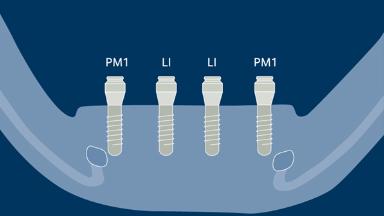

- outline recommendations for configuration of implants supporting a complete overdenture

- identify the degree of prosthesis support according to implant configuration

- select appropriate attachment types for denture retention